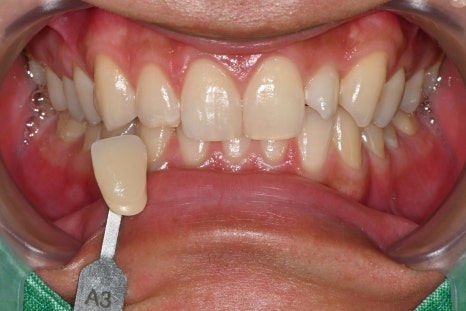

오브제로 라미네이트

< 미백 전 A3 > 미백 후 A1 >

미백 전에는 치아 색이 A3 톤으로 다소 어두웠고,

미백 후에는 확실히 밝아졌습니다.

이 과정이 중요한 이유는,

오브제로 라미네이트의 색을

인접 치아와 자연스럽게 맞추기 위해서입니다.

라미네이트가 아무리 정교해도

주변 치아과 색 차이가 있으면 인위적으로

보일 수밖에 없습니다.